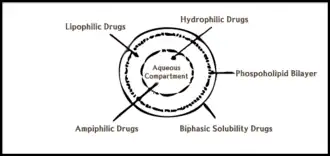

Liposomes

Liposomes are a common vehicle in drug delivery and specifically for the treatment of cancer. Liposomes contain a phospholipid bilayer. It is prevalent due to its ability to penetrate leaky vasculature and poor lymphatic drainage within tumors for enhanced permeability retention.[37] These drug carriers can encapsulate hydrophobic and lipophilic molecules within their lipid bilayer and can be made naturally or synthetically.[38][39] In addition, liposomes can entrap hydrophilic molecules in their hydrophilic core.[38] Compared to the common cancer treatment chemotherapy, drugs loaded into liposomes allow for decreased systemic toxicity and a potential increase in the efficacy of targeted delivery.[18] Success with liposomes as drug delivery systems has been shown both in vivo and in vitro.[38] A study by Liu et al. showed that liposomes can be used alongside SDT to trigger the release of drugs via oxidation of the lipid components.[40] Another study by Ninomiya et al. utilized nanoemulsion droplets exposed to ultrasonic waves for the formation of larger gas bubbles to disrupt the liposome membrane for drug release. Many properties and elements of liposomes can be altered for their specific purpose and to increase effectiveness, particularly their ability to travel in the blood and interact with cells and tissues in the body.[38] These elements include their diameter, charge, arrangement, as well as the makeup of their membranes.[38] Dai et al. proposed the incorporation of sonosensitizers with liposomes to enhance target specificity.[18] Since SDT stimulates cancerous tissues to absorb and retain sonosentizers followed by activation with extracorporeal ultrasound, Dai et al. investigated the effect of liposome-encapsulated drugs on the efficacy of targeted delivery in SDT. They found that, in addition to its convenience and practicality, SDT is a safe and effective option for treating cancer.[18]